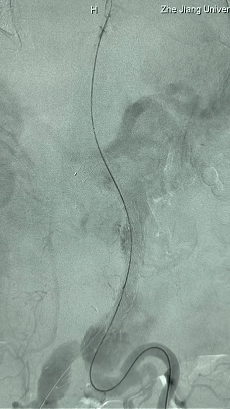

1. 患者平卧位,麻醉成功后,留置导尿,常规术野消毒铺巾。左侧肘部切开,暴露左侧肱动脉,置入6F鞘。双侧股动脉穿刺,分别置入10F鞘,全身肝素化。

2. 左侧肱动脉入路,超选至降主动脉,更换8F-900mm长鞘,造影提示IV型胸腹主动脉瘤,累及双肾动脉。